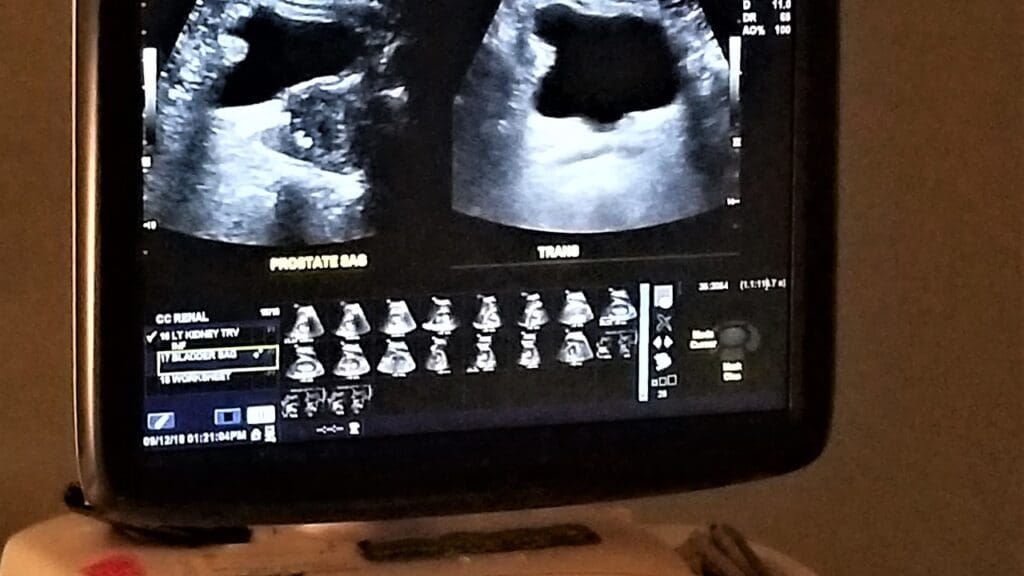

What to Expect During US Aorta Screening

A healthcare expert will use a transducer to send sound waves to the aorta. These waves bounce back, creating images on a screen. The test is done in hospitals, clinics, or mobile units.

Patients lie on their back during the test. A gel might be used on the belly to help sound waves. The whole process is painless and doesn’t use radiation.

The technician will look at the aorta’s size. They check for any swelling that’s not normal.

Interpreting Ultrasound Images

A radiologist or healthcare expert will look at the images. They check for aneurysms by measuring the aorta’s size. If it’s over 3 cm, it’s considered an aneurysm.

The images also show the aneurysm’s shape and where it is. This info helps decide how to treat it.

It’s important to understand these images well. They help diagnose AAA and plan treatment. If an aneurysm is found, more tests or monitoring might be needed.